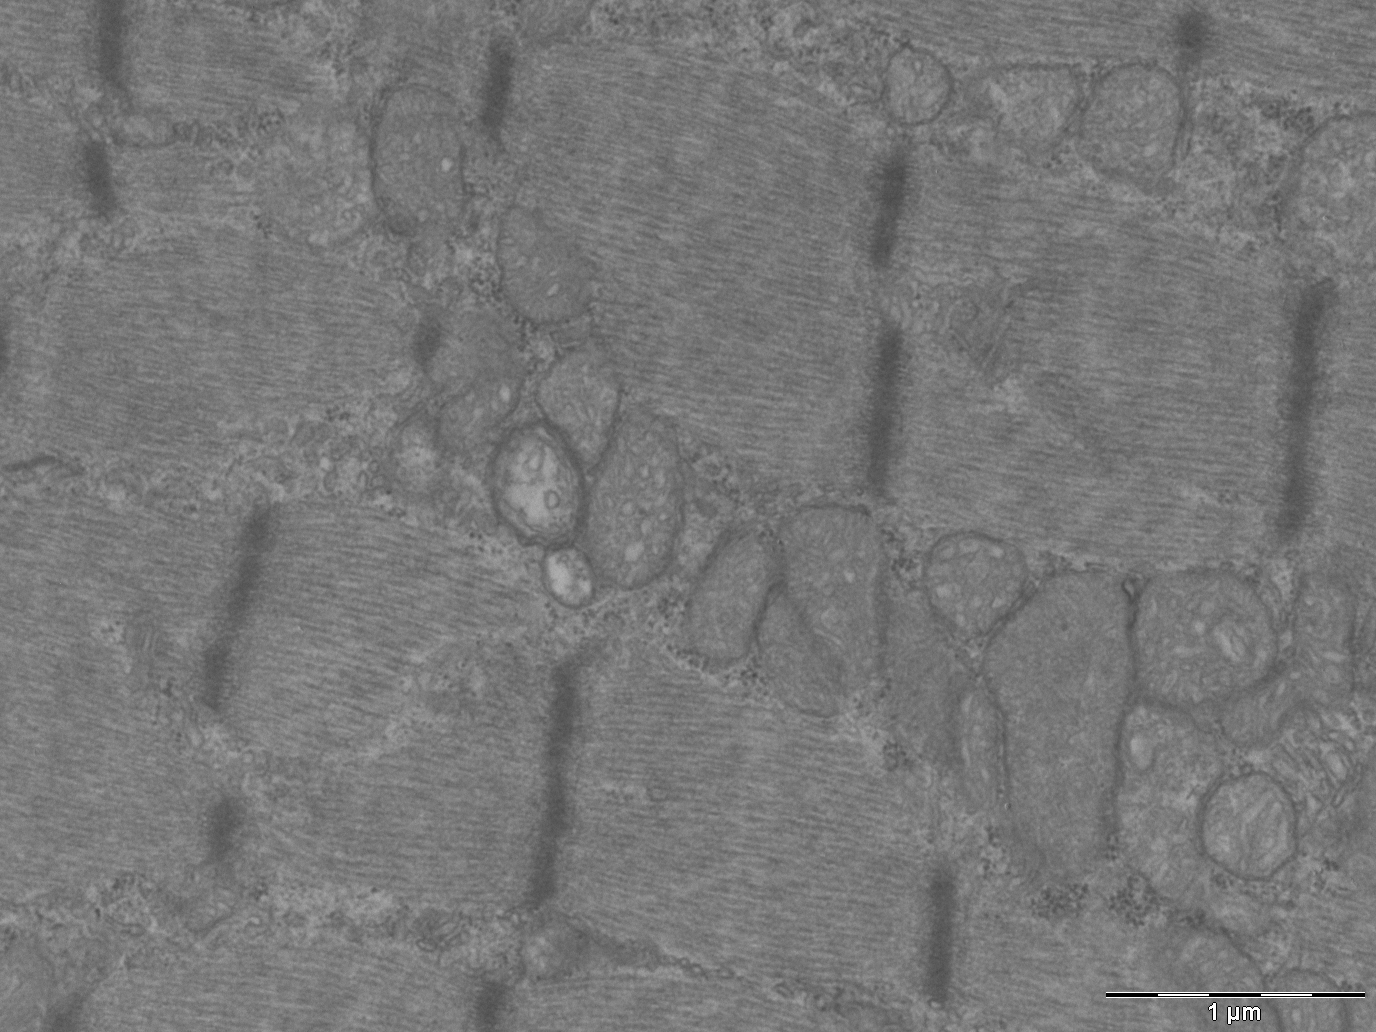

La Vanguardia, Diario Médico, GEN, Technology Networks, entre altres mitjans de comunicació nacionals i internacionals, han publicat un article sobre un treball recent de l’IRB Barcelona que obre la via a considerar que defectes en els mitocondris poden estar en l’origen d’un grup de malalties que impliquen inflamació muscular crònica i que tenen un origen desconegut.